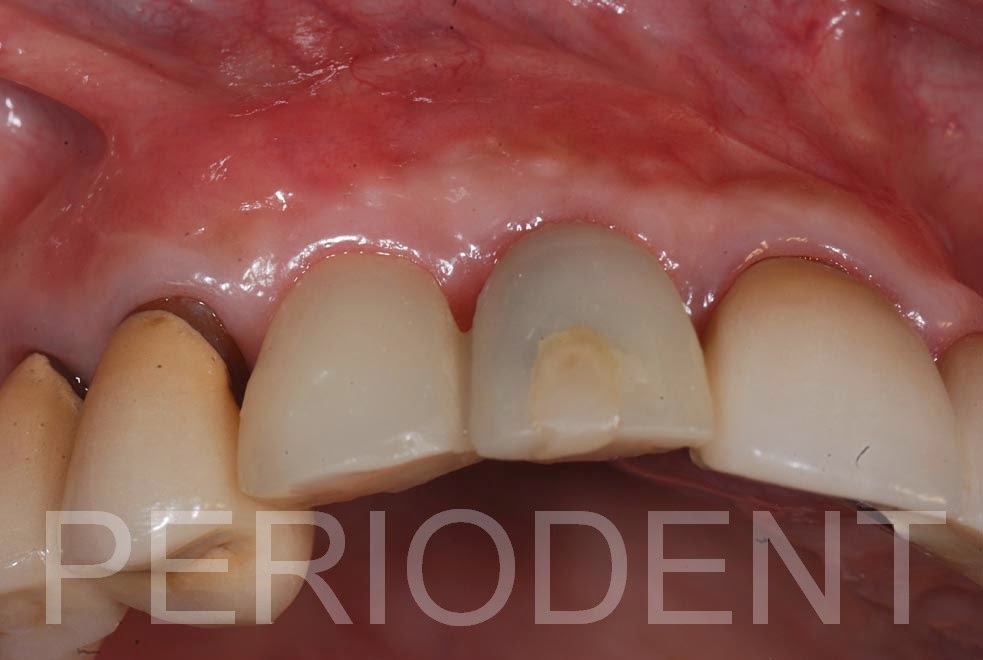

重新調整臨時假牙

植牙手術前